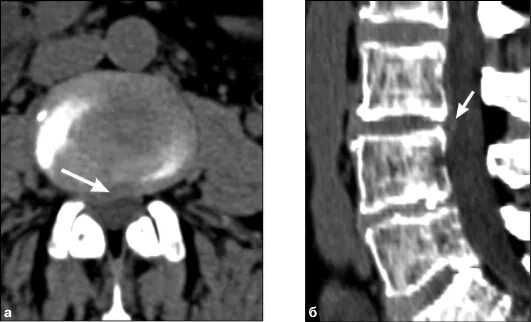

Грыжи на кт